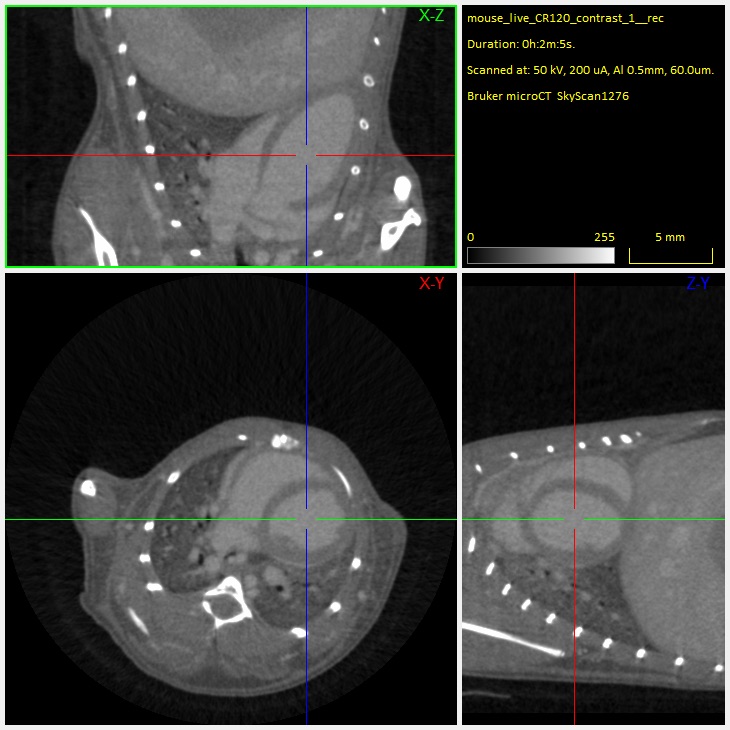

The SKYSCAN 1276 CMOS Edition is a high performance, stand-alone, fast, desktop in vivo microCT with continuously variable magnification for scanning small laboratory animals (mice, rats, ...) and biological samples. An optional Large Animal Transport System (LATS) is available which enables the system to mount also large animals including rabbits.

The SKYSCAN 1276 CMOS Edition has an unrivalled combination of high resolution, big image size, round and spiral (helical) scanning and reconstruction, and low dose imaging. The image field of view up to 75 mm wide and 310 mm long allows full body mouse and rat scanning. The variable magnification allows scanning bone and tissue samples with high spatial resolution down to 2.8 μm pixel size. Variable X-Ray energy combined with a range of filters ensures optimal image quality for diverse research applications from lung tissue to bone with metal implants. The system can perform scanning with continuous gantry rotation and in step-and-shoot mode with scanning cycles down to 3.9 sec. Furthermore, the SKYSCAN 1276 CMOS in vivo microCT administers a low radiation dose to the animals allowing multiple scans in longitudinal preclinical studies without the risk of unwanted radiation-induced side effects. The fully integrated physiological monitoring package allows monitoring and controlling the animal's wellbeing at all times through a video stream, ECG, temperature and breathing detection.